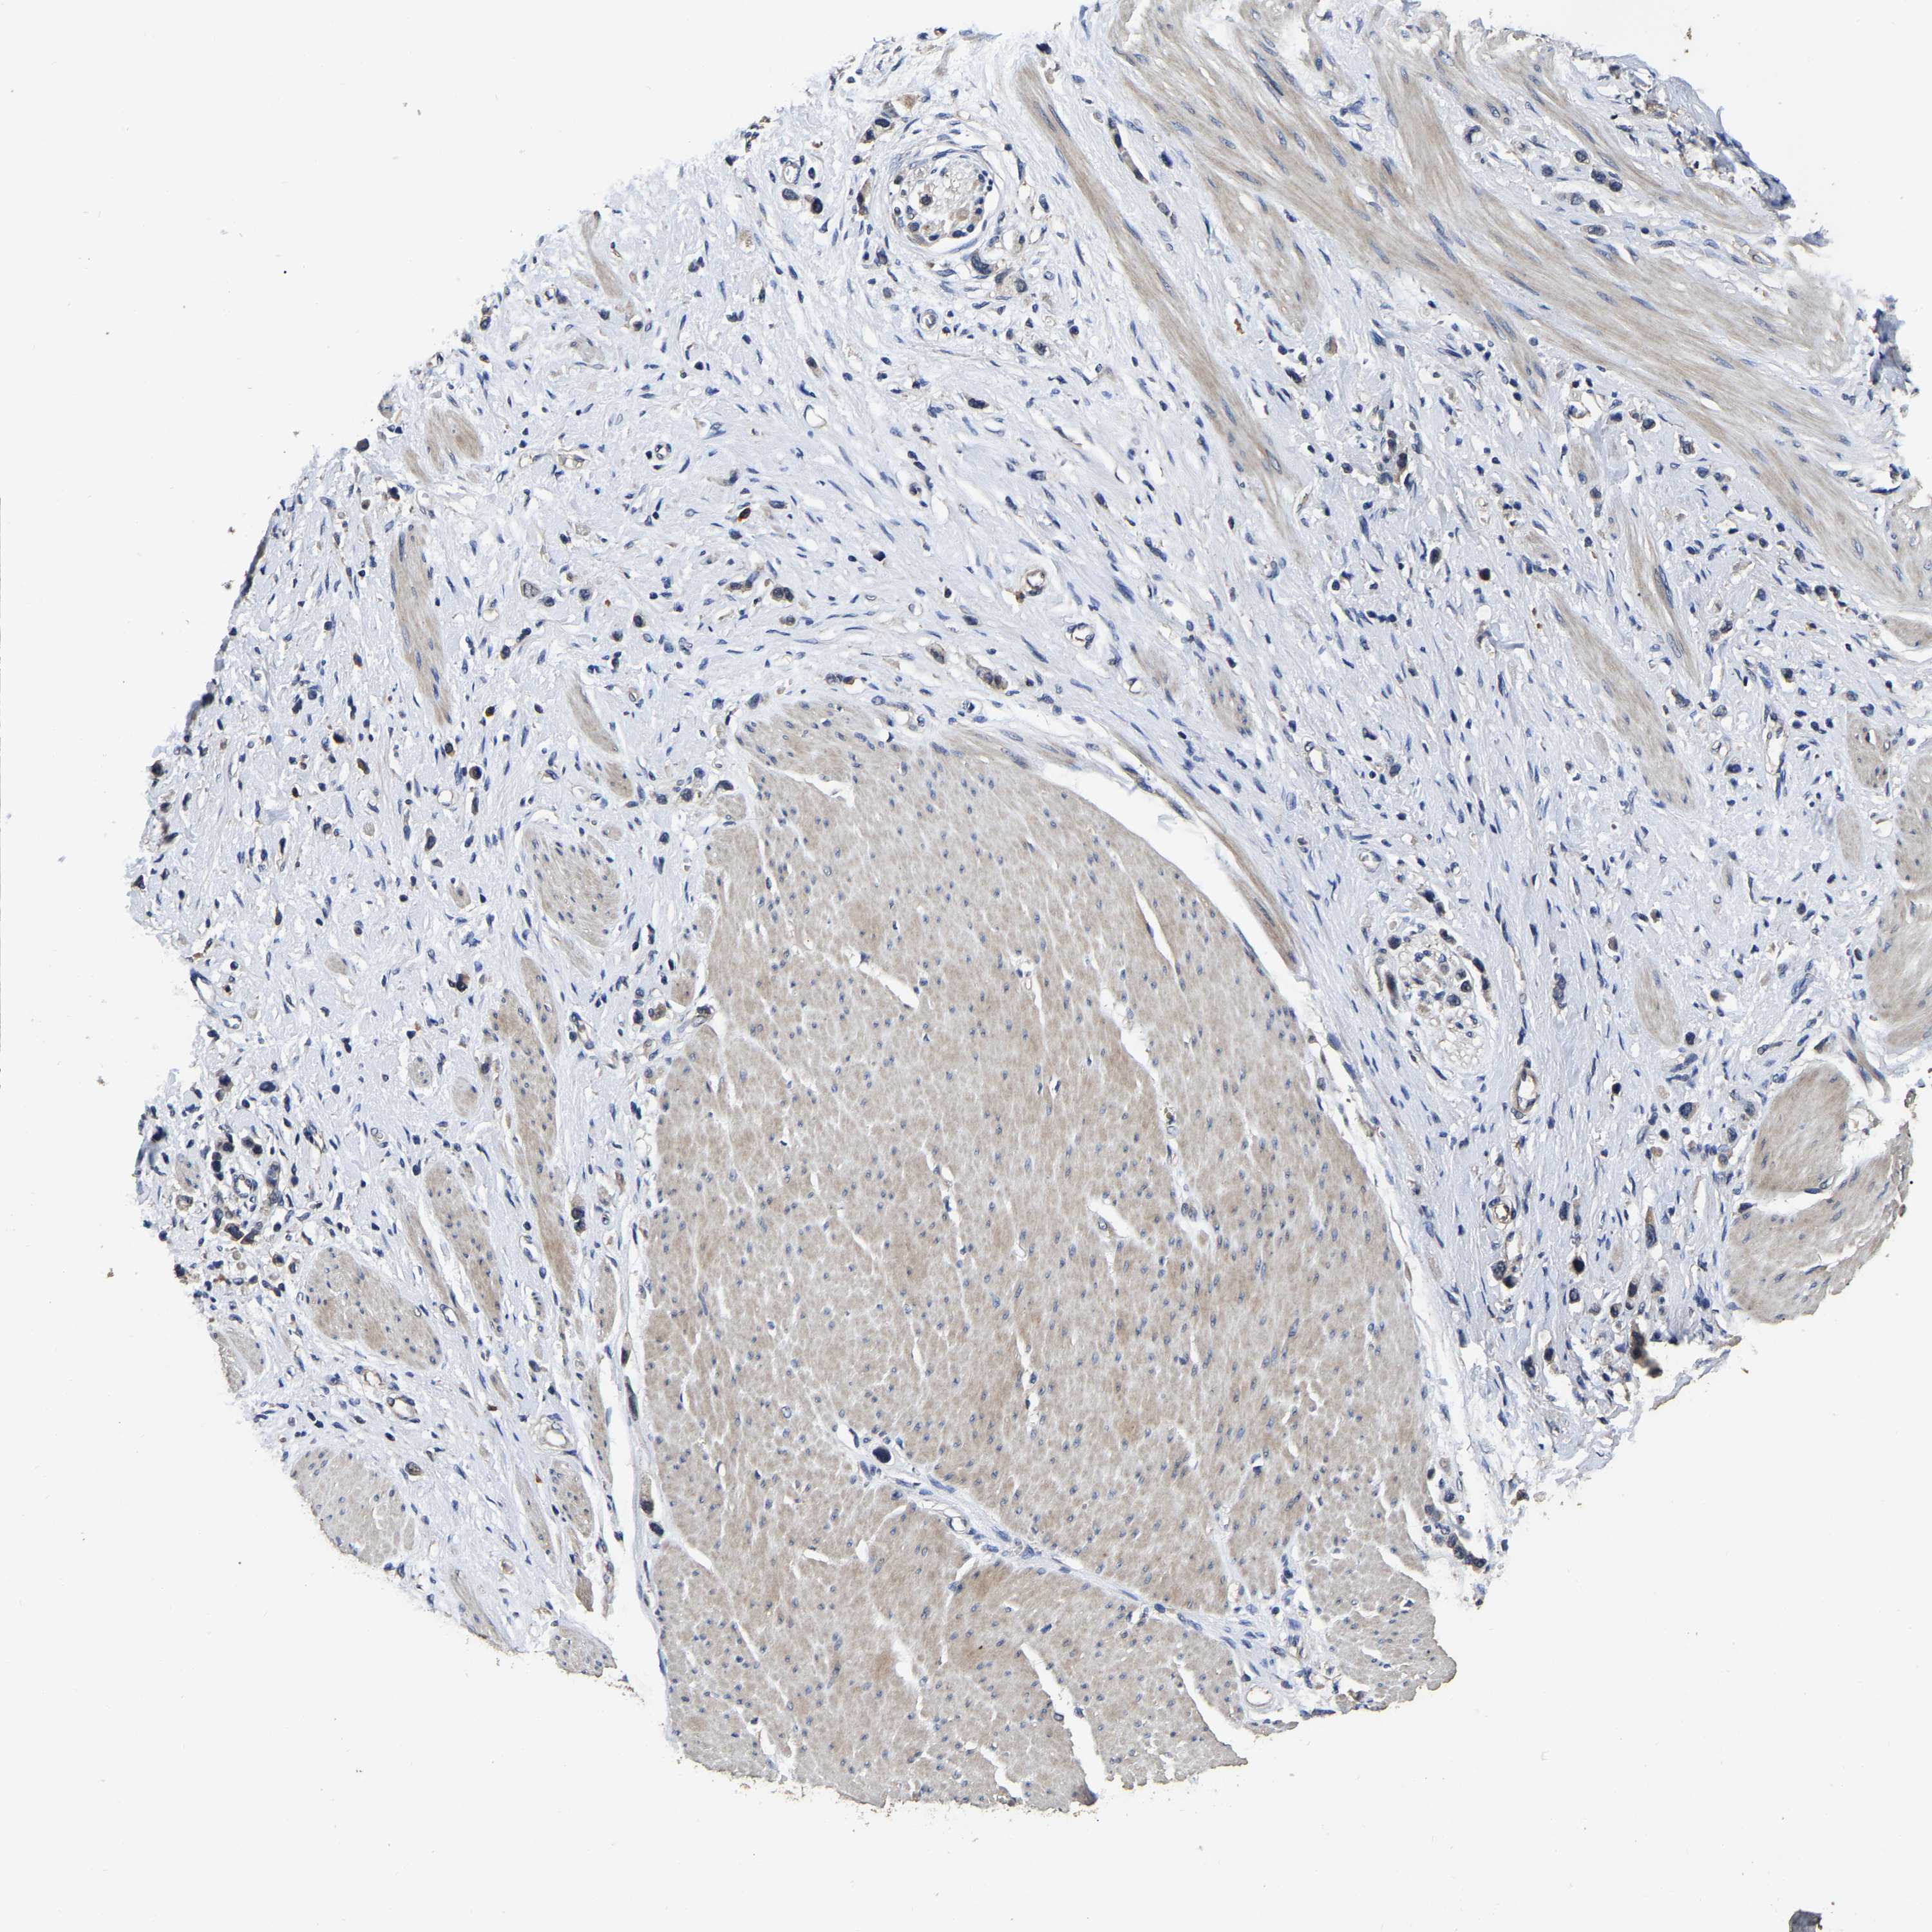

STOMACH CANCER - Protein expressioni

A mouse-over function shows sample information and annotation data. Click on an image to view it in a full screen mode. Samples can be filtered based on level of antibody staining by selecting one or several of the following categories: high, medium, low and not detected. The assay and annotation is described here.

Note that samples used for immunohistochemistry by the Human Protein Atlas do not correspond to samples in the TCGA dataset.

Antibody stainingi

Antibody staining in the annotated cell types in the current human tissue is reported as not detected, low, medium, or high, based on conventional immunohistochemistry profiling in selected tissues. This score is based on the combination of the staining intensity and fraction of stained cells.

Each image is clickable and will lead to virtual microscopy that enables deeper exploration of all samples and also displays staining intensity scores, fraction scores and subcellular localization as well as patient and tissue information for each sample.

Antibody HPA017894

Staining

High

Medium

Low

Not detected

Intensity

Strong

Moderate

Weak

Negative

Quantity

>75%

75%-25%

<25%

None

Location

Nuclear

Cytoplasmic/membranous

Cytoplasmic/membranous,nuclear

Adenocarcinoma, NOS